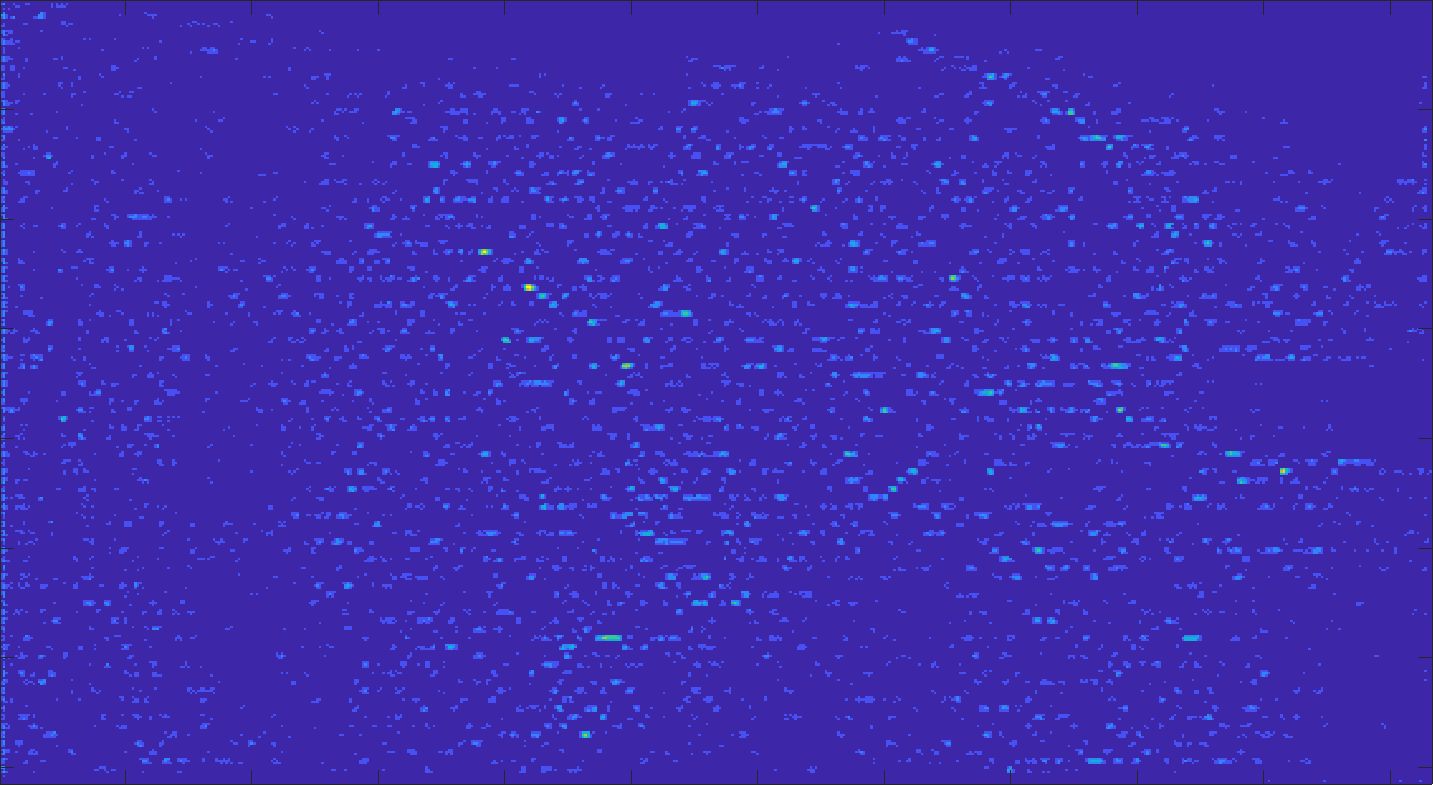

Our framework visually improves the results, in terms of blurring and artefacts. This result is more evident in the magnification of the ear of the foetus (Fig. 3), the mitral valve (Fig. 4), and the mass edges (Fig. 5). Fig. 6 shows the error image of the three anatomical districts with both 2X and 4X up-sampling factors, with the maximum error in the scale . The error is more evident in the contours of the anatomical structures; moreover, the abdominal district shows a smaller error than the cardiac and obstetric ones. We underline that the view for each image is scaled to its maximum, to improve the visualisation of the error.

The analysis of the absolute value of the difference between the input and the prediction of the network (Fig. 9) shows that the alteration of our prediction to the pixel values ranges from 0 to a maximum absolute value of 20, mainly located on the edges of the anatomical structures; furthermore, the black uniform areas are less affected by the prediction. In terms of the distance between the input and the prediction, we do not observe a significant difference among anatomical districts and between 2X and 4X up-sampling.